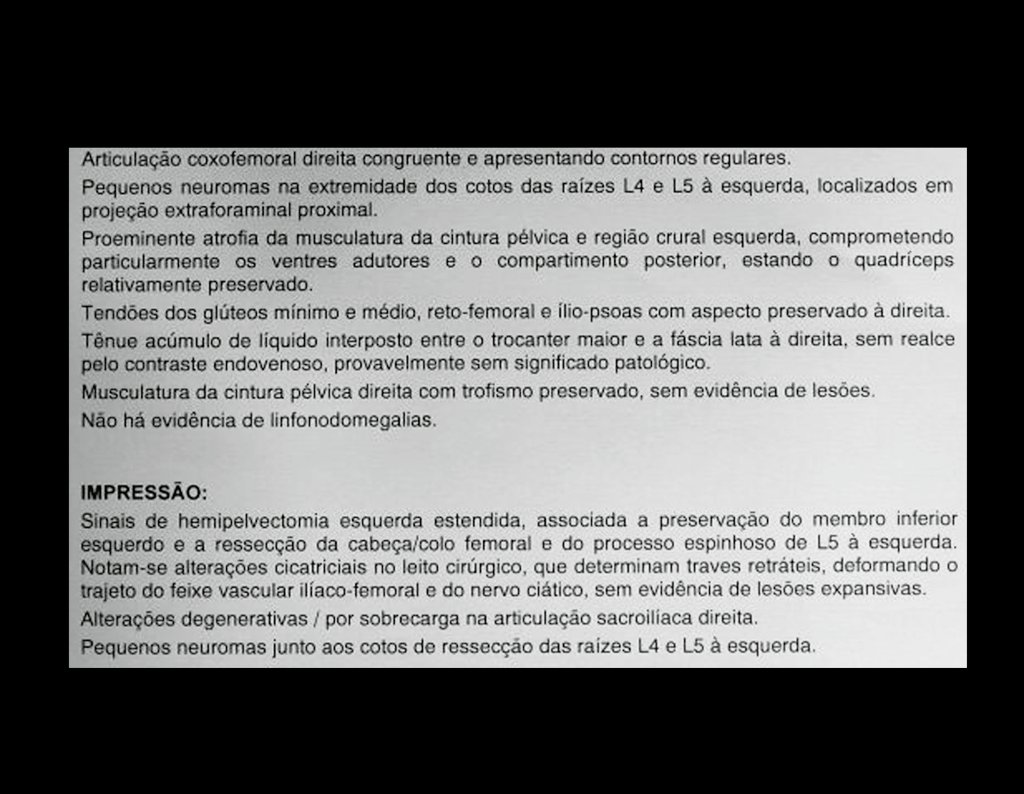

Ressonância Magnética (RM)

- RM axial e coronal em T1: Apresentou baixo sinal com grande tumor extra cortical, comprometendo a tábua interna e externa do ilíaco direito.

- RM axial e coronal em T2: Sinal alto com grande tumor extra cortical.

- RM axial T1 spir: Com supressão de gordura, evidenciou reação periosteal em espículas e focos de calcificação.

- RM axial T1 com saturação de gordura e contraste: Mostrou uma espessa área de captação devido à capa de cartilagem neoplásica maligna ao redor da lesão.

- Dois anos pós-operatório: RM sem sinais de recidiva, bom aspecto local.

- Três anos pós-operatório: Paciente sem sinais de recidiva, bom resultado funcional e cosmético, compensação com calçado.

- Quatro anos pós-operatório: Estabilidade da discrepância do MIE, excelente recuperação funcional.

- Doze anos e três meses pós-operatório: Paciente exibiu uma vida sem limitações significativas, superando o déficit funcional e exercendo atividades diárias com desenvoltura.